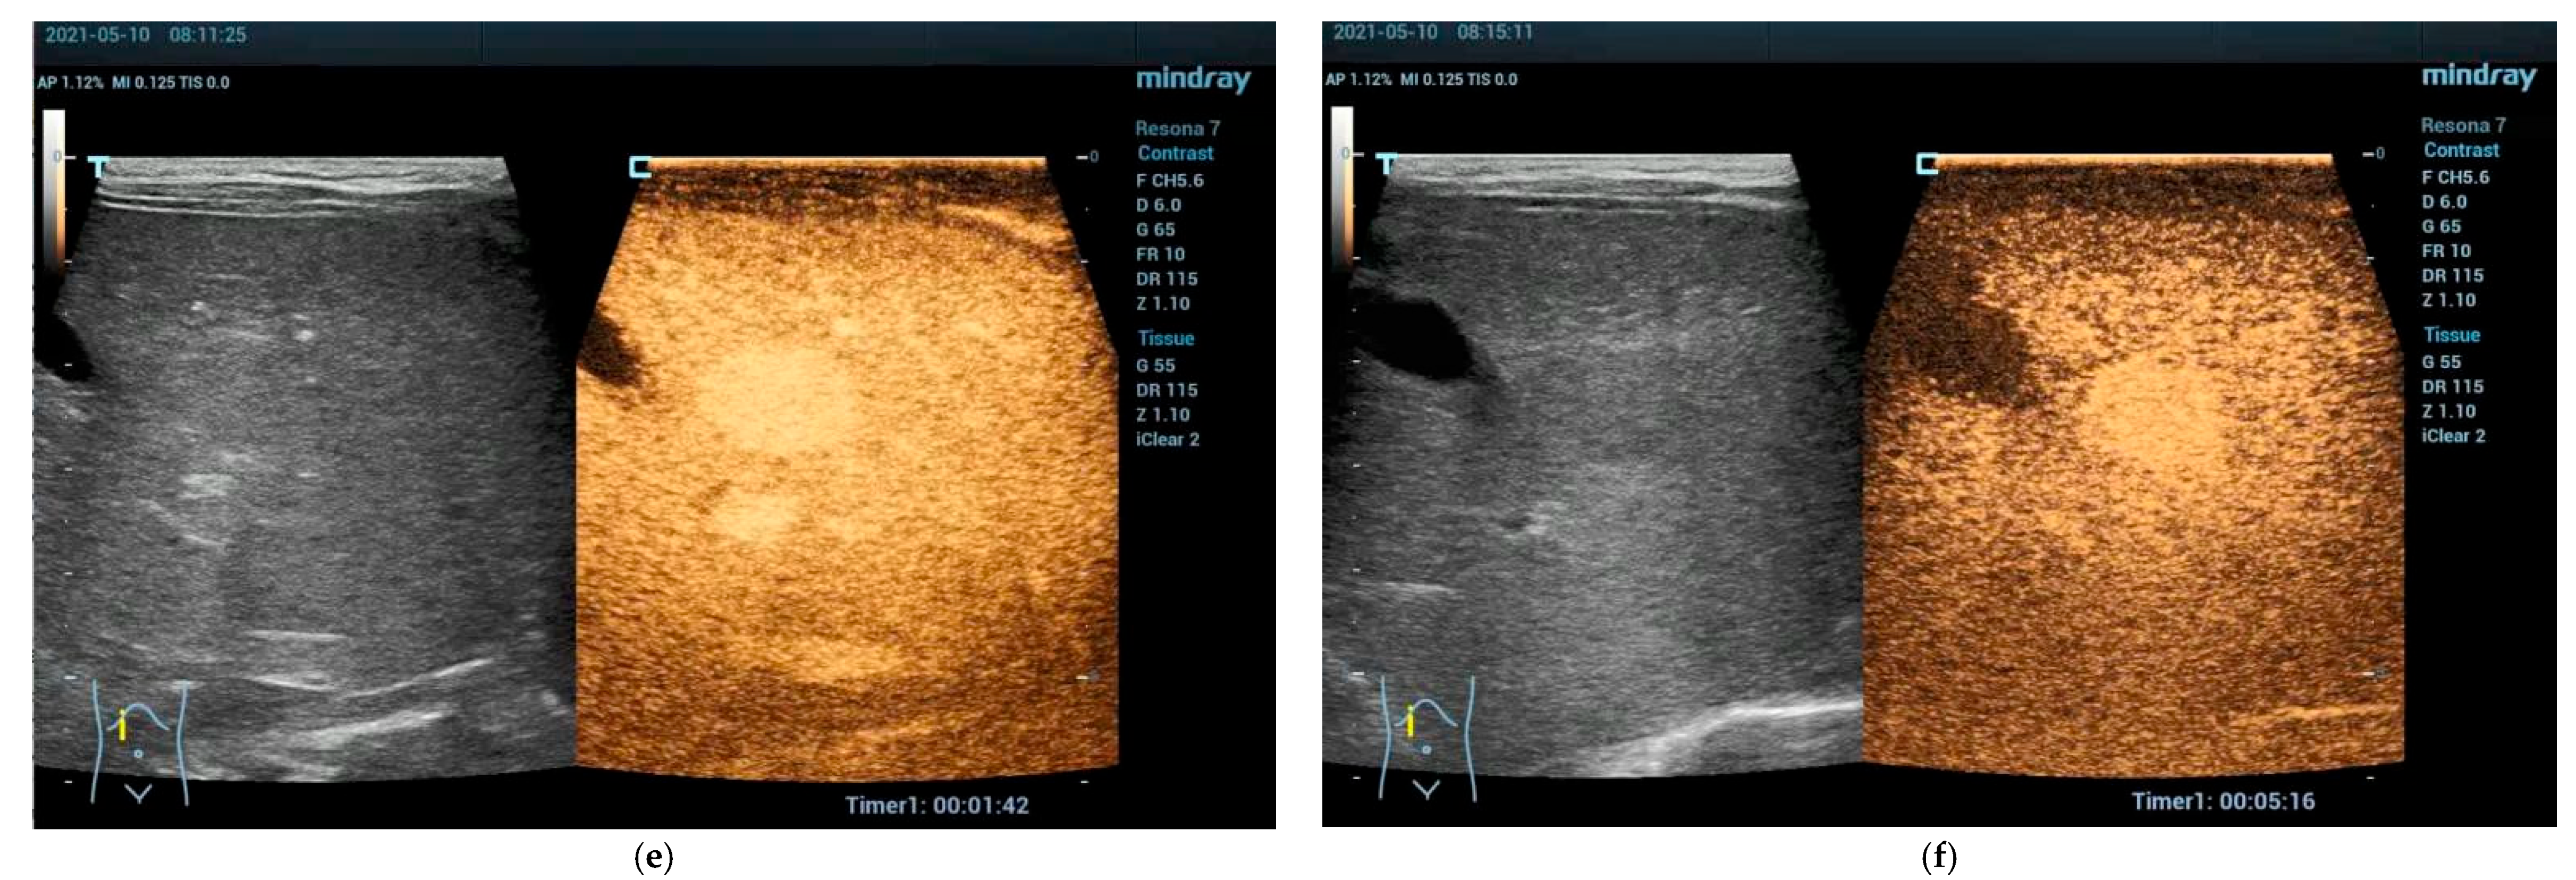

4.3.1. Hepatic Hemangioma

4.3.2. Congenital Hepatic Hemangioma

4.3.3. Infantile Hepatic Hemangioma

4.4. Vascular Malformations Other than Hemangioma

Focal Nodular Hyperplasia (FNH)